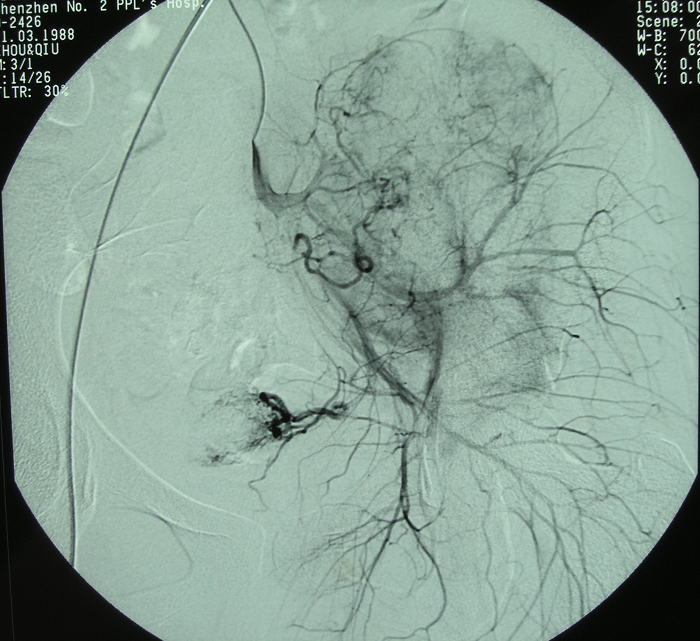

6、病例6:女 18岁 左半骨盆骨肉瘤,全身及肿瘤局部选择性动脉灌注大剂量化疗后行肿瘤切除人工半骨盆假体置换术

图 39 术前DSA